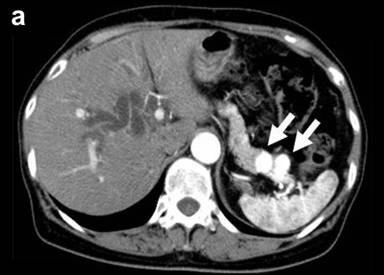

A 67-year-old female was referred to our hospital, complaining of jaundice, appetite loss and 3 kg of body weight loss over one month. She had undergone a thyroidectomy for a thyroid adenoma and a right oophorectomy for an ovarian tumor at 41 years of age and a right nephrectomy for renal cell carcinoma at 47 years of age. Laboratory data demonstrated mild liver dysfunction due to obstructive jaundice without elevation of plasma CEA and CA 19-9 levels. Computed tomography (CT) demonstrated a remarkably enhanced tumor measuring 55x40 mm in diameter in the head, two tumors measuring 2.0 and 1.8 cm in the body, and two tumors measuring 1.2 and 1.0 cm in the tail with a similar enhancing effect (Figure 1abc). CT angiography did not demonstrate any abnormalities of the arteries and the dorsal pancreatic artery branching from the origin of the splenic artery (Figure 1d). Magnetic resonance imaging demonstrated obstruction on the intrapancreatic bile duct due to a pancreatic head tumor and a slight dilatation of the main pancreatic duct in the body and tail of the pancreas. Fluorine-18 fluorodeoxyglucose positron emission tomography detected an elevated uptake in the isolated multifocal metastatic pancreatic tumors without any extrapancreatic uptake. A biliary drainage tube was inserted endoscopically. Cytology of the pancreatic juice was negative. The patient was diagnosed with isolated pancreatic metastases from renal cell carcinoma. The huge tumor located in the head was resected by a pancreaticoduodenectomy and the four tumors located in the body and in the tail of the pancreas were resected by a distal pancreatectomy, preserving the cervical portion. Intraoperative confirmation of arterial perfusion in the middle segment was necessary. In other cases, a total pancreatectomy should be done. Enucleation was not considered due to the risk of main pancreatic duct injury.

Figure 1. Preoperative computed tomography. Pancreatic metastatic tumors were detected as being demarcated enhanced tumors in the tail (a.) and body (b.) of the pancreas. A very large tumor occupied the entire head of the pancreas (c.). The common bile duct was compressed by the tumor located in the head of the pancreas (d.). |